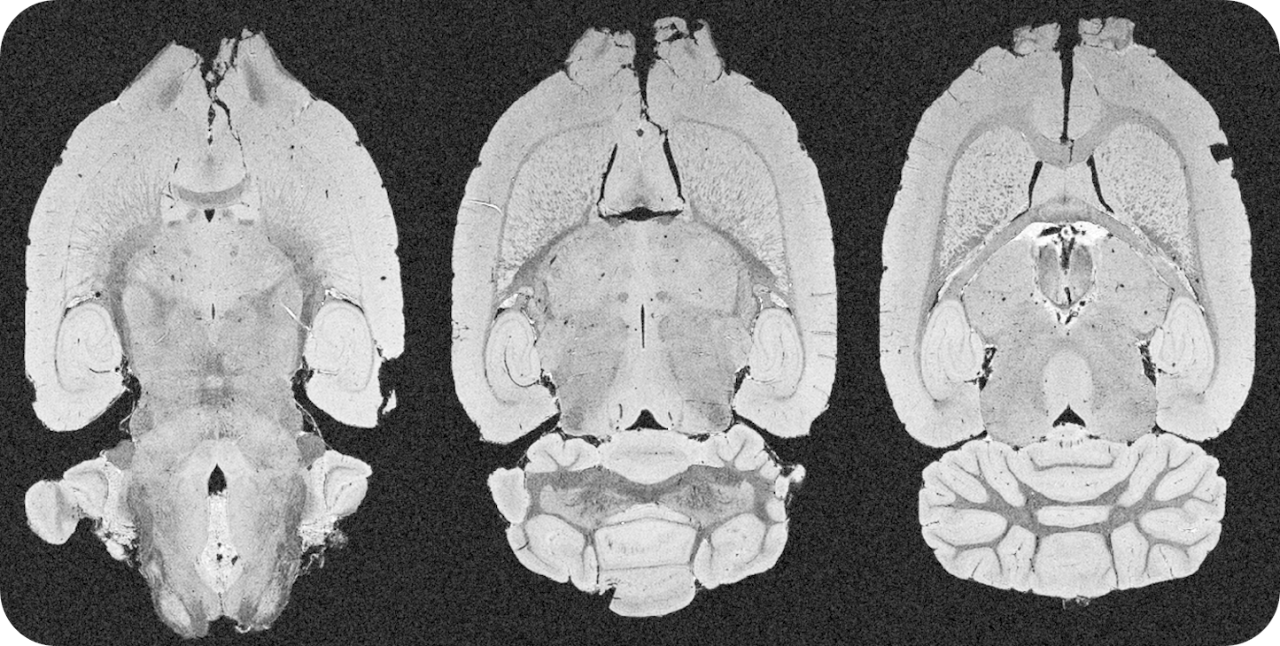

An extremely powerful instrument for most challenging murine imaging studies

The ultra-high field of the BioSpec 152/11 provides extreme sensitivity for greatest resolution. Its streamlined design for mice studies makes handling simple, while its powerful software guarantees best results. It can be equipped with the MRI CryoProbe to increase sensitivity even further and together with the gradient strength of up to 1000 mT/m, highest resolution is achieved. It is built with nitrogen-free Ultra Shielded and helium Refrigerated (US/R) magnet technology for long service intervals

• Crisp and highly resolved images with native gradient strength of 740 mT/m, upgradable to 1000 mT/m

• MRI CryoProbe for exceptional increase in sensitivity